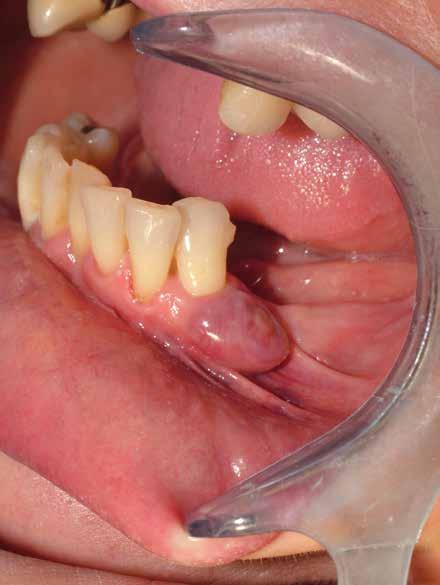

Alla visita di rivalutazione è emerso un ulteriore peggioramento della situazione, confermata anche dall’esame radiografico, con parodontopatia, sanguinamento al sondaggio, infiammazione diffusa, alitosi, difetto parodontale verticale mesiale a 2.3, residui radicolari 1.4, 1.6, 1.7, 3.6, 3.8 e carie destruenti di 1.5, 2.6, 3.5, 3.7 (con lesione endoperio) e 4.7 con estrusione e carie (Figg. 1, 2)

Si è consigliato di procedere per gradi, con bonifica di tutti gli elementi malati e irrecuperabili e successivamente sostituire gli elementi mancanti o con protesi rimovibili o con una protesi fissa sostenuta da impianti (Fig. 3).

La proposta che il paziente ha accettato è stata poi quella, previa bonifica di tutti gli elementi irrecuperabili, di riabilitare con impianti prima il 1° e 4° quadrante e in seguito il 2° e 3° e procedere poi alla protesi definitiva in un’unica soluzione.